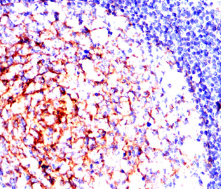

IHC    1/200 - 1/1000